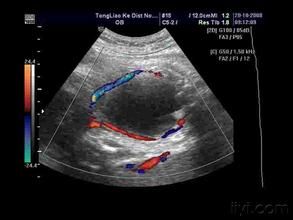

胎兒腎積水正常胎兒腎臟的集合系統可有輕度分離,分離徑可達6毫米,而胎齡大於30周后腎盂擴張≥10毫米或存在腎小盞擴張則為腎積水。腎積水分為兩種。一種為可復性:積水寬度1.01—1.63厘米之間,腎實質較厚,1.02—0.58厘米之間,胎兒出生後環境變化,積水隨之消失。常見於胎兒的膀胱內大量尿液充盈或某種原因引起的輸尿管收縮節律失調。另外部分病例的輸尿管可能存在某些解剖結構的異常。另一種為不可復性:積水寬度2.15—2.56厘米,腎實質厚0.3—0.2厘米,常見於先天性輸尿管狹窄,多有分泌功能的變化,出生後應及時治療。

綜上所述,全面了解胎兒腎積水的轉歸,定期隨訪尤為重要。如胎兒腎積水寬度0.58厘米,可視為正常;如積水寬度>2.15厘米或腎實質厚度<0.2厘米為不可復性,可視情況終止妊娠。